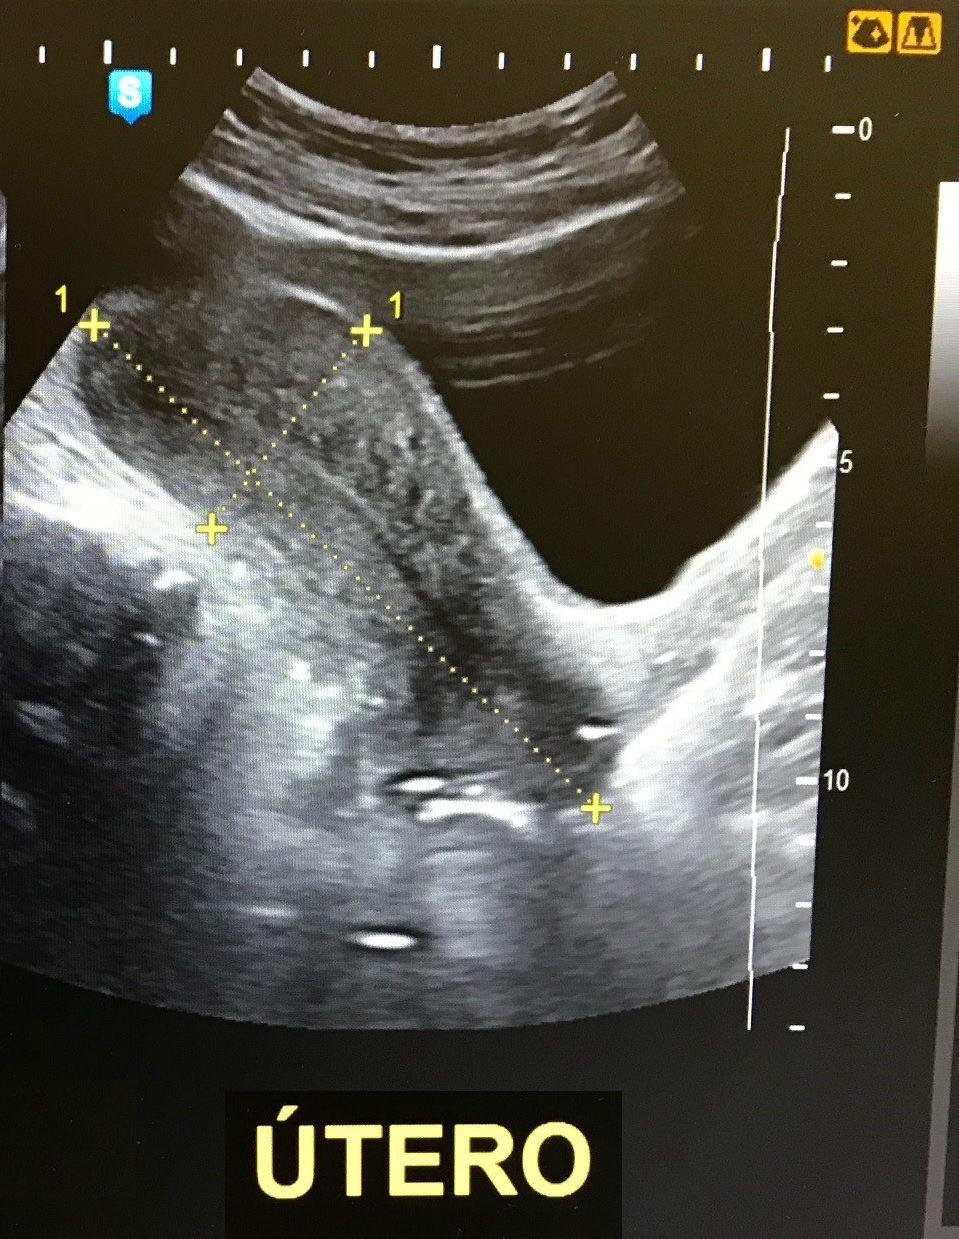

Na atenção à mulher, hoje é insubstituível o papel da ultrassonografia transvaginal no diagnóstico de patologias pélvicas femininas e da ultrassonografia mamária, como um estudo complementar essencial à mamografia.

Temos papel inovador na região sul do estado, com a realização de exames transvaginais para pesquisa de endometriose profunda, doença que acomete até 10% da população feminina em idade fértil.

ULTRASSONOGRAFIA OBSTÉTRICA E FEMININA

Pesquisa de Endometriose